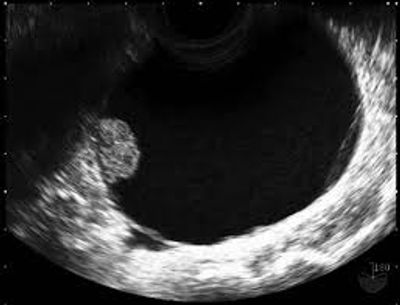

Typical benign ovarian cyst